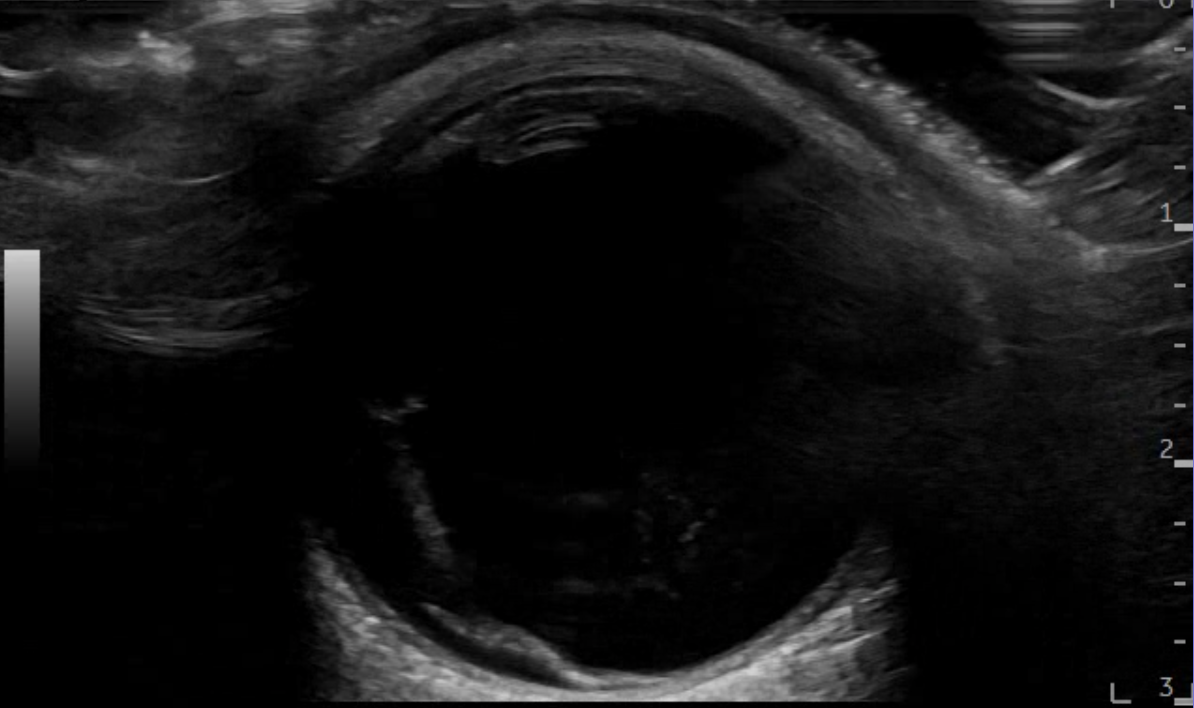

En urgencias hospitalarias se valora presión intraocular de ojo derecho en 12 mmHg y se realiza ecografía clínica del ojo con sonda plana, apreciando la imagen de sospecha de desprendimiento de vítreo posterior al apreciar una capa flotante en la porción posterior del mismo que en condiciones normales, no debería visualizarse.

Dado que la paciente no tiene antecedentes personales ni factores de riesgo cardiovascular, no parece corresponderse con una degeneración macular ni un desprendimiento de retina, aunque sí parece impresionar de un desprendimiento de vítreo posterior como posible causa inicial.